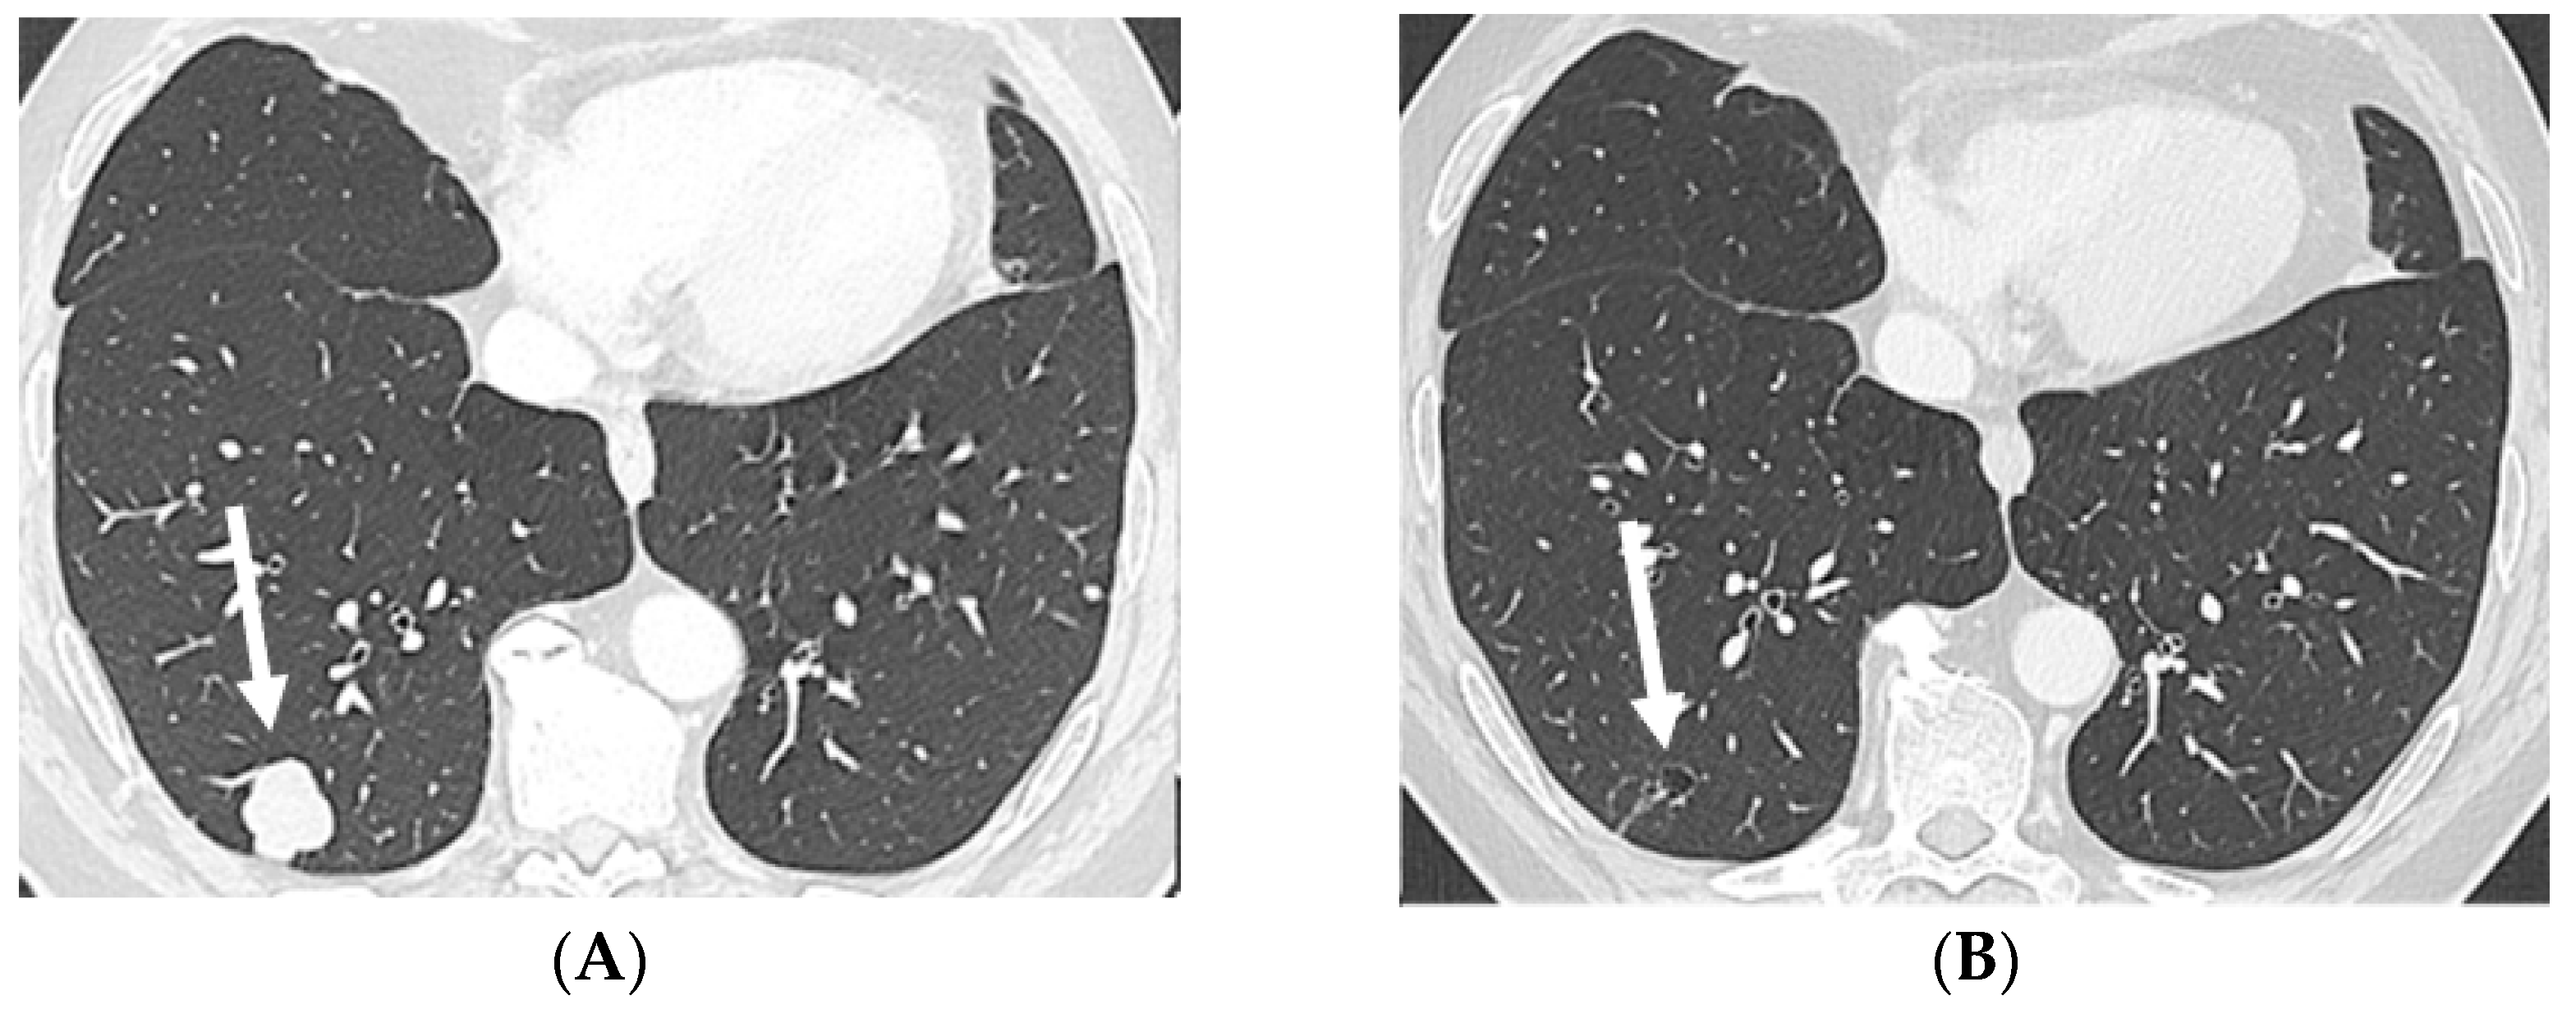

2.2. Case 2